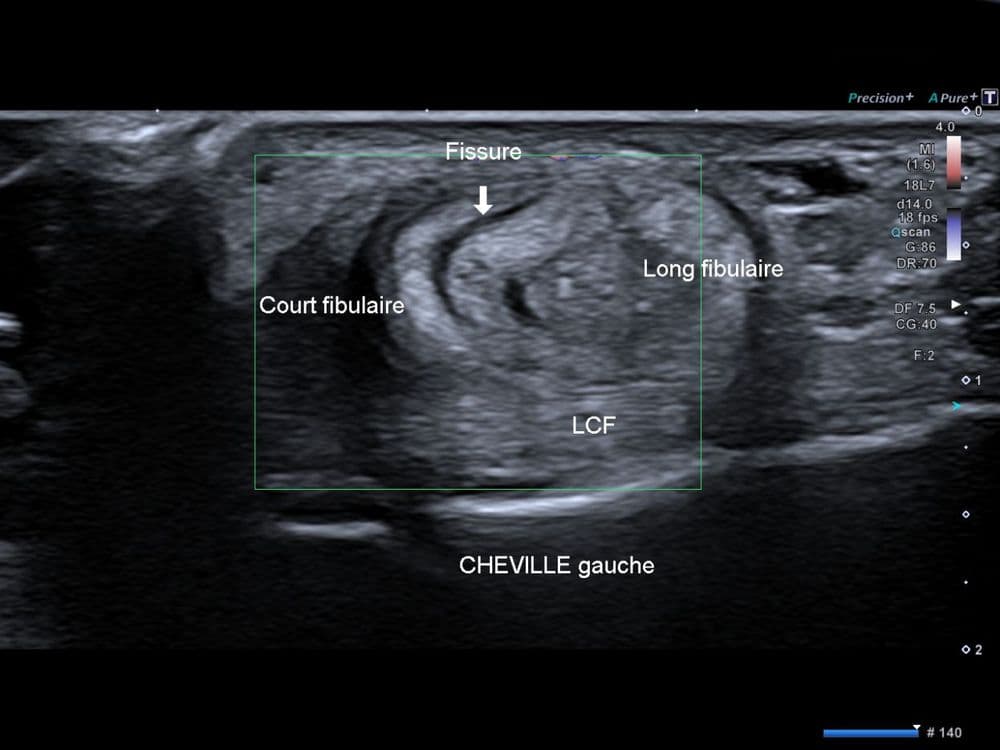

Douleur non traumatique latérale à la cheville, exacerbée par l'activité physique.

US

Tendon surnuméraire issu des muscles fibulaires situés dans la loge latérale de la jambe.